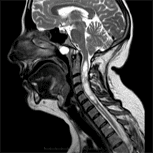

Patologia del Filum, frequente e sconosciuta